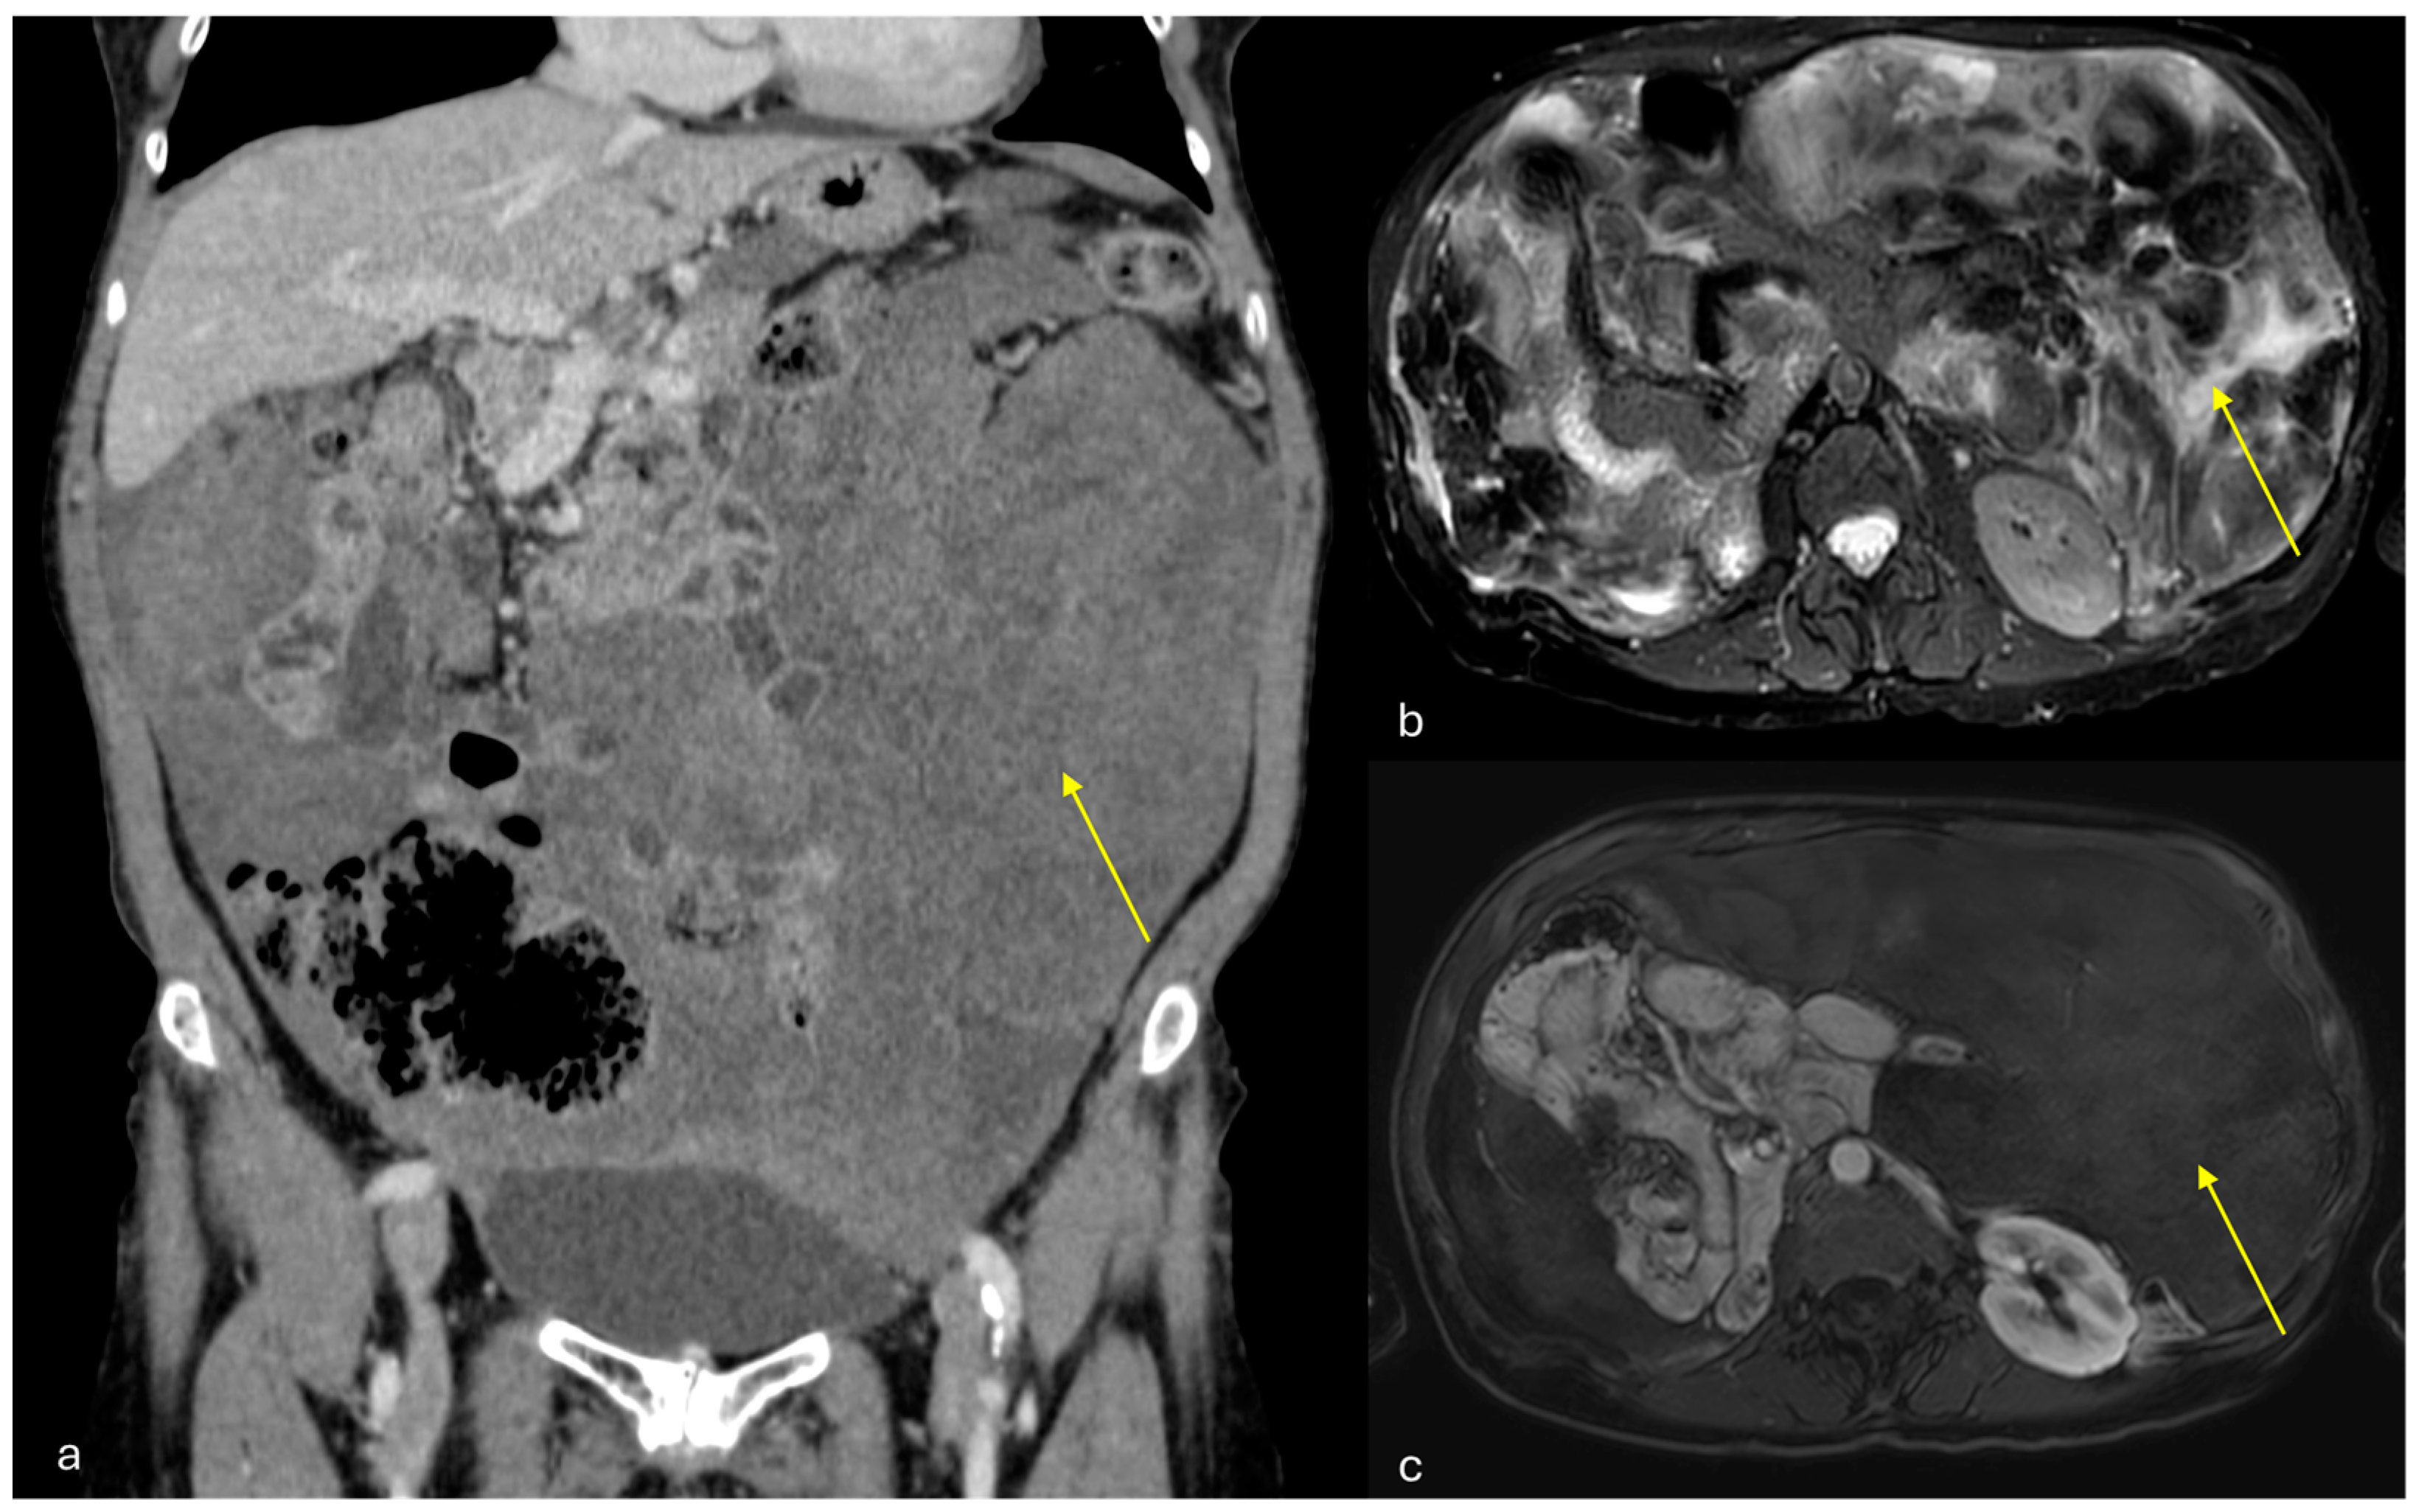

- Micro-nodular pattern: micro-nodules with a diameter ≤ 5 mm (Figure 1);

- Nodular pattern: nodules with a diameter > 5 mm (Figure 2a);

- “Omental cake”: nodular thickening of the omentum (Figure 2b);

- Plaque pattern: confluent nodular plaques, typically involving the lower surface of the right diaphragm (Figure 3);